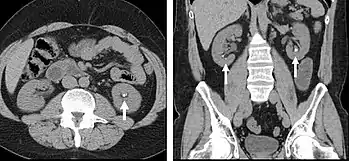

Detection and characterization of renal parenchymal masses is a frequent indication for CT. An initial noncontrast CT is important for detecting calcium or fat in a lesion, and to provide baseline attenuation of any renal masses. Following noncontrast scanning, intravenous contrast is injected and a corticomedullary phase is obtained at approximately 70 seconds (figure 7a, 7b). The corticomedullary phase is characterized by enhancement of the renal cortex as well as the renal vasculature. This phase is valuable in the evaluation of benign renal variants, lymphadenopathy and vasculature, however certain medullary renal masses may not be visible during this phase due to minimal enhancement of the medulla and collecting system. The parenchymal phase is obtained approximately 100–200 seconds after the injection of contrast material (figure 7c). Parenchymal phase imaging demonstrates continued enhancement of the cortex, enhancement of the medulla, and various levels of contrast material in the collecting system. The parenchymal phase is highly important for the detection and characterization of renal masses, parenchymal abnormalities, and the renal collecting system. This method of imaging does not evaluate for abnormalities of the collecting system.

Common renal masses can occasionally be differentiated from each other using this imaging technique. Renal cell carcinomas and oncocytomas typically demonstrate intense heterogeneous enhancement on the parenchymal phase images and cannot be reliably differentiated from each other but can be distinguished from other renal masses. Angiomyolipomas (AML’s) also demonstrate intense contrast enhancement but characteristically contain macroscopic fat which can be detected on the noncontrast images, and can help to differentiate AML’s from renal cell carcinomas and oncocytomas. Renal lymphoma on the other hand, will often have decreased enhancement when compared to the renal parenchyma on the parenchymal phase images.

FIGURE 7. Selected images from a renal mass specific protocol CT. Corticomedullary phase (axial 7a) demonstrates peripheral enhancement of the renal cortex with minimal opacification of the renal medulla. There is a large renal cell carcinoma in the left kidney (right in image) which can be differentiated from the normal renal parenchyma by the heterogeneous and differential enhancement. The renal artery and vein are opacified in this phase as well. The collecting system is not opacified (coronal reformat 7b). In the parenchymal phase, the renal cortex and the medulla are enhancing. The renal cell carcinoma in the left kidney is not as well defined when compared to the corticomedullary phase images, but is actually slightly more conspicuous. There is some contrast noted within the collecting system during this phase (7c).